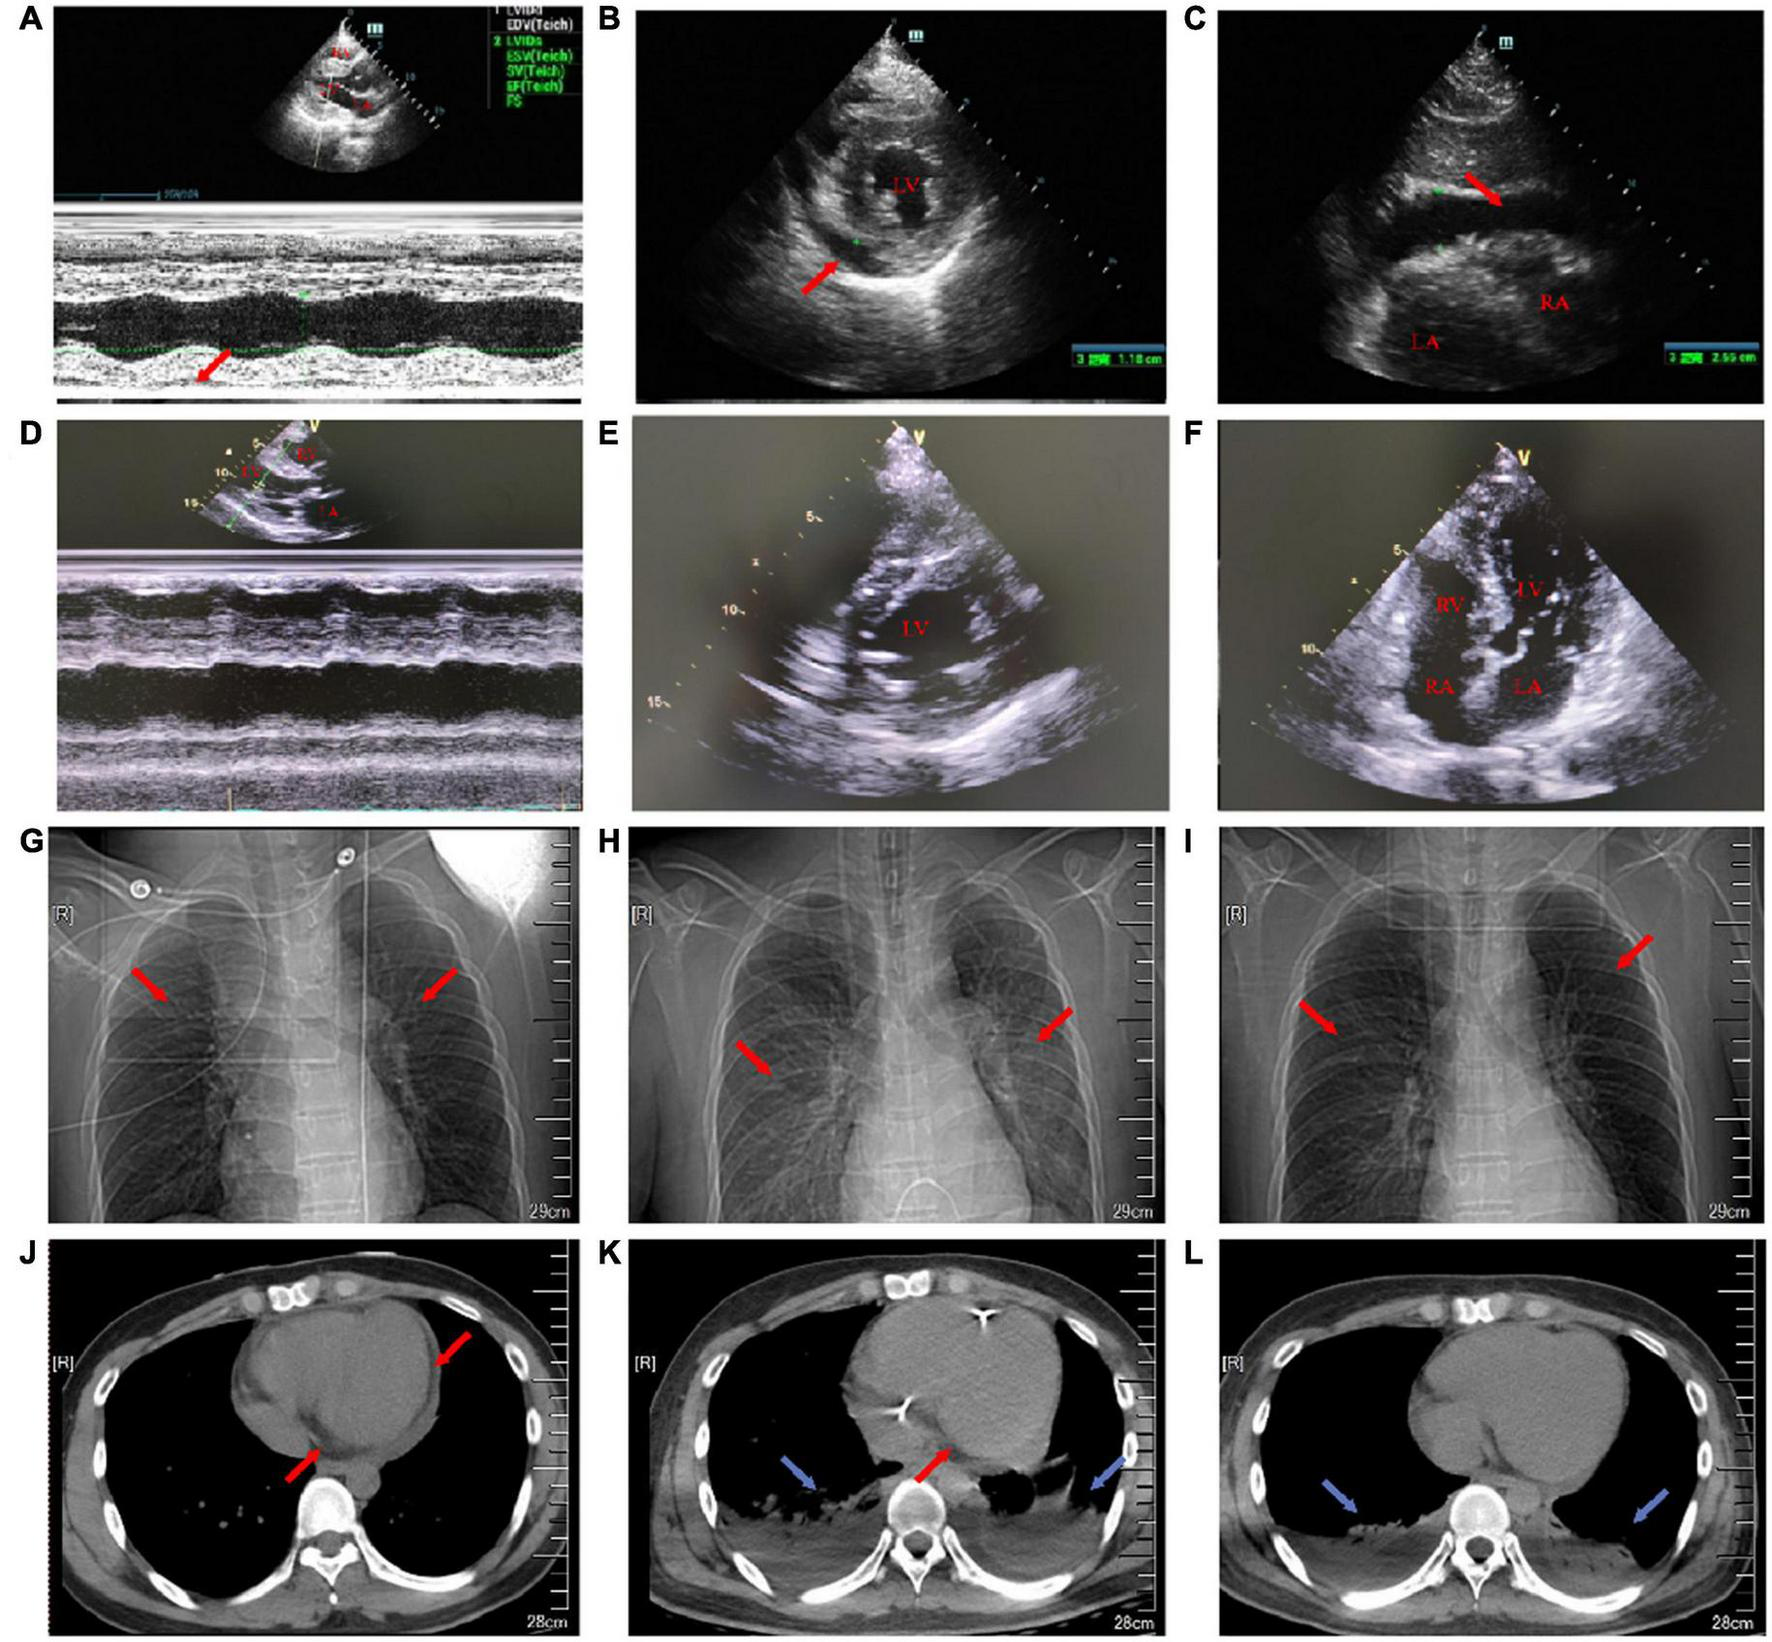

FIGURE 2

Transthoracic echocardiography on the first day and the 18th day of admission. Chest X-ray and chest CT images on the first, eighth, and 15th day of admission. (A) On the first day of admission, the maximum anterior–posterior diameter of the posterior dark area of the left ventricular posterior wall on the long-axis view of transthoracic echocardiography was 0.8 cm (red arrow). (B) On the first day of admission, the maximum anterior–posterior diameter of the dark area of the lower wall of the left ventricle on the short-axis view of transthoracic echocardiography was 1.2 cm (red arrow). (C) On the first day of admission, transthoracic echocardiography showed that the anterior–posterior diameter of the dark area under the xiphoid process was 2.5 cm (red arrow). (D) On the 18th day after admission, the pericardial effusion on the long-axis view of transthoracic echocardiography was less than that before. (E) On the 18th day after admission, the pericardial effusion on the short-axis view of transthoracic echocardiography was less than that before. (F) On the 18th day of admission, transthoracic echocardiography four-chamber view. (G) On the first day of admission, a chest X-ray showed a few fibrous foci in both the lungs (red arrow). (H) On the eighth day of admission, the chest X-ray showed inflammation in the upper lobe of the left lung and the middle lobe of the right lung (red arrow). (I) On the 15th day of admission, the chest X-ray showed a little inflammation of the left upper lung (red arrow). (J) On the first day of admission, the cross-section of the chest CT soft-tissue window showed that the pericardial fat space was blurred and there was a large amount of pericardial effusion (red arrow). (K) On the eighth day of admission, the cross-section of the chest CT soft-tissue window showed bilateral pleural effusion with bilateral lower lung insufficiency (blue arrow) and a small amount of pericardial effusion (red arrow). (L) On the 15th day of admission, the cross-section of the chest CT soft-tissue window showed bilateral pleural effusion and bilateral lower lung insufficiency (blue arrow).

In the emergency department, his vital signs and physical examination were as follows: body temperature (T) 38.4°C, respiratory rate (RR) 23 beats/min (bpm), blood pressure (BP) 106/72 mm Hg, pulse (P) 98 bpm, oxygen saturation (SpO2) 98% (indoor air), pupil diameter 2 mm, and sensitive bilateral light reflex. No swelling of superficial lymph nodes is found in the whole body. The breath sounds of both the lungs were thick during auscultation and no dry and wet rales were heard. The heart rate (HR) was 98 bpm, the heart sound was low and dull, and there was no murmur in each valve area. The abdomen was flat and soft, the Murphy sign was negative, the liver, spleen, and subcostal were not reached, there was no edema in both the lower limbs, and the pathological sign was negative. Admission laboratory tests showed (Supplementary Table 1): leukocyte count 6.75 × 10Λ 9/L, neutrophils 68.2%, lymphocytes 18.7%, eosinophils 0.3%, amylase 24 U/l, total bilirubin 27.6 μmol/l, direct bilirubin 13.3 μmol/l, blood potassium 3.5 mmol/l, creatinine 107.5 μmol/l, random blood glucose 7.51 mmol/l, cardiac troponin I (cTnI) 38.678 ng/ml, N-terminal B-type natriuretic peptide (NT-proBNP) 8,480 ng/ml, creatine kinase (CK) 1,203 U/l, creatine kinase-MB (CK-MB) 55 U/l, lactate dehydrogenase (LDH) 406 U/l, alanine aminotransferase (ALT) 21 U/l, aspartate aminotransferase (AST) 114 U/l, and procalcitonin (PCT) 0.47 ng/ml. ECG showed: sinus rhythm, right bundle branch block, and ST-segment elevation in leads II, III, aVF, and V2–V6 (diffuse) (Figure 1A). Transthoracic echocardiography showed pericardial effusion [the maximum anterior–posterior diameter of the posterior dark area of the left ventricular posterior wall was 0.8 cm (Figure 2A), the maximum anterior–posterior diameter of the dark area of the left ventricular inferior wall was 1.2 cm (Figure 2B), and the anterior–posterior diameter of the dark area of the xiphoid process was 2.5 cm (Figure 2C)] and the left ventricular systolic function decreased [left ventricular ejection fraction (LVEF) = 42%]. Brain CT showed no abnormality. Chest CT showed a few fibrous foci in both the lungs (Figure 2G). Massive pericardial effusion and blurred pericardial fat space are also present, considering the possibility of inflammatory lesions (Figure 2J). Abdominal CT showed intrahepatic bile duct calculi.

On the seventh day of admission, the patient’s body temperature decreased and the level of anaerobic metabolism in arterial blood further decreased (pH 7.43, PaCO2 33 mm Hg, PaO2 90 mm Hg, HCO3– 21.9 mmol/l, BE– 1.9, and Lac 1.9 mmol/l), suggesting that organ perfusion was improved and relevant laboratory indexes tended to be improved (Figure 4). ECG showed that sinus rhythm and diffuse ST-segment elevation were significantly improved (Figure 1B). Echocardiography showed that the pericardial effusion decreased gradually (less to medium, the maximum anterior–posterior diameter of the dark area of the lower wall of the left ventricle was 0.8 cm) and the left ventricular systolic function was higher than that of front (LVEF = 47%). Color Doppler ultrasound of the thoracic cavity showed bilateral pleural effusion (2.6 cm on the left and 4.3 cm on the right). Brain CT showed no abnormality. Chest CT showed inflammation in the upper lobe of the left lung and the middle lobe of the right lung (Figure 2H), bilateral pleural effusion and bilateral lower lung insufflation (Figure 2K), and a small amount of pericardial effusion. Abdominal CT showed changes in peritoneal exudation and pelvic effusion. Considering the reduced demand for mechanical support, they stopped CRRT support.

Before discharge, the patient’s body temperature was normal and there was no discomfort such as headache and chest tightness. Re-examination of ECG suggested sinus rhythm and ST-T changes (Figure 1C). Echocardiography indicated that the size of each cardiac cavity was normal, the movement of the ventricular wall was normal, and the ventricular systolic function was normal (LVEF = 59%) (Figures 2D–F). The patient’s chest CT showed little inflammation in the upper left lung (Figure 2I), bilateral pleural effusion, and bilateral lower lung insufficiency (Figure 2L). He was discharged from the hospital on the 21st day of admission and returned home without apparent complications. During the 3-year follow-up period, he had no deterioration of cardiac function, recurrent myocarditis, congestive heart failure, or episodes of ventricular arrhythmias.